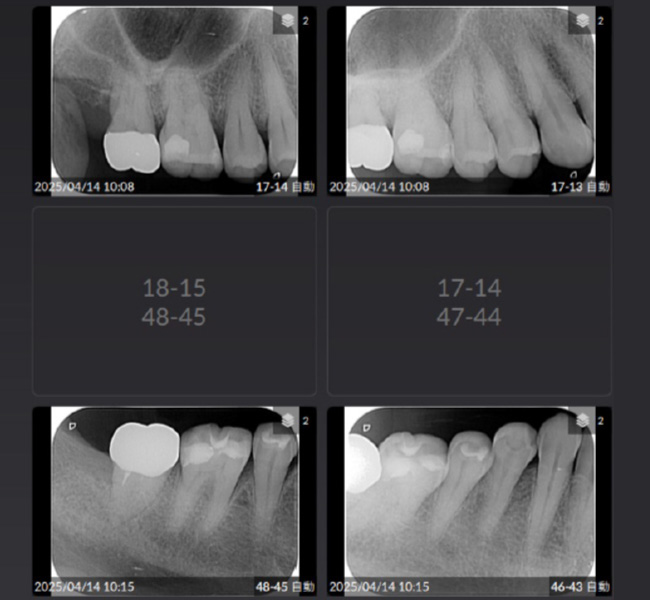

治療前

| 治療内容 | 全顎治療:歯周病治療、根管治療、 歯肉弁剥離掻爬術(フラップ手術)、 セラミック治療、ダイレクトボンディング |